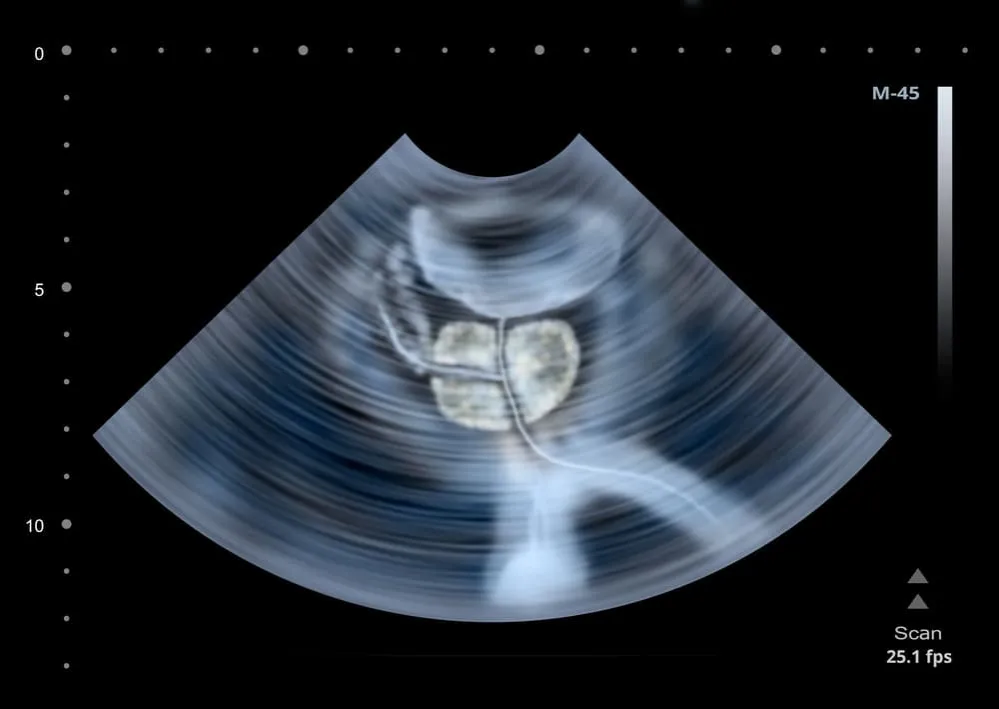

Czym jest badanie TRUS i dlaczego daje tak precyzyjny obraz prostaty?

USG transrektalne (TRUS) to badanie ultrasonograficzne wykonywane przez odbytnicę. Dzięki temu, że sonda ultrasonograficzna znajduje się bardzo blisko prostaty, możliwe jest uzyskanie bardzo dokładnego i precyzyjnego obrazu gruczołu krokowego. Lekarz może ocenić jego wielkość, strukturę wewnętrzną, a także zidentyfikować wszelkie podejrzane zmiany, takie jak guzki czy obszary o zmienionej echogeniczności, które mogą wymagać dalszej diagnostyki.

- Lekarz będzie przesuwał sondę, aby dokładnie obejrzeć prostatę pod różnymi kątami, a obraz będzie widoczny na monitorze.